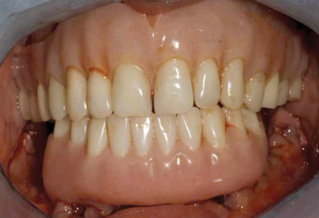

This is an unfortunate mindset in that current advances in protocol and technology can result in significant advantages in addressing some or most of these concerns. The patient shown in Figure 12 may serve to illustrate this point. She had a destroyed maxillary dentition, a less-compromised but highly unesthetic mandibular component, and a single goal: to be able to "smile at my grandchildren again." In consultation with her and her family, it was decided that a double-arch fixed implant approach would most realistically address her esthetic goals and provide her with the desired prosthetic result. She was 102 years old at the time of initial consultation. Using a staged operating-room approach, provisional restorations were initially delivered, followed by subsequent definitive hybrid final restorations. She was able to use these comfortably for the next 6-½ years (Figure 13 and Figure 14).

Fig 12. Treatment to restore this patient’s smile and functionability commenced when she was 102 years old.

Figure 12

Fig 13. An All-on-4 approach was used to treat both arches with interim immediate and eventual definitive restorations.

Figure 13

Fig 14. Final restorations used for 6-1/2 additional years.

Figure 14